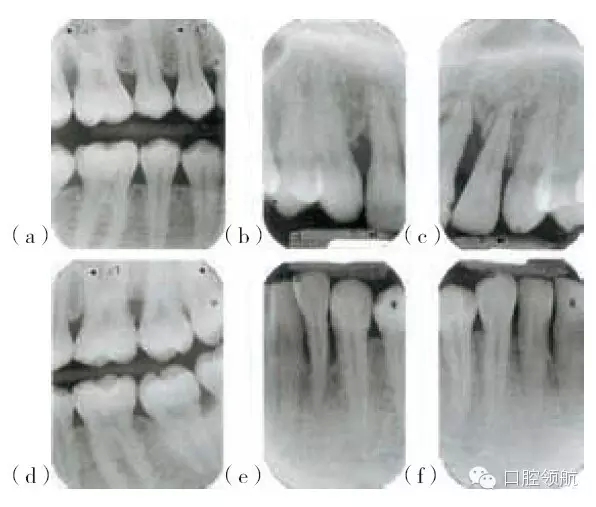

圖29.5 (a,d)圖29.4患者的X線片,咬合面的X線片顯示上頜第一磨牙遠(yuǎn)中及下頜左側(cè)

第二磨牙,有齦下牙石和牙槽骨吸收。(b,c,e,f)根尖片顯示右上側(cè)切牙,左上中切

牙及側(cè)切牙,左下側(cè)切牙有齦下牙石及牙槽骨吸收